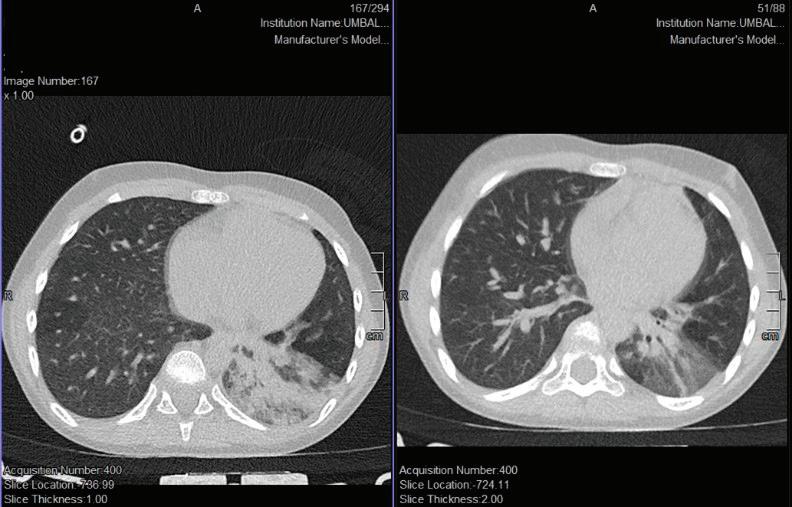

паренхим и КАТ на глава – без данни за патологични отклонения. Предвид липсата на корелация между тежкото клинично състояние и несигнификантно изменените параклиникнични показатели – рентгенография без патологични отклонения - се проведе КАТ на бял дроб. От КАТ на бял дроб се установява образ, който на рентгенографията не се визуализира: възпалителен инфилтрат в 10 сегмент вляво с тенденция към консолидация и дилатирани съдове, вероятна хиперемия. Единични медиастинални лимфни възли, Фиг. 1 и Фиг. 2

Фиг. 1 Рентгенография бял дроб

Фиг. 2 КТ гръден кош